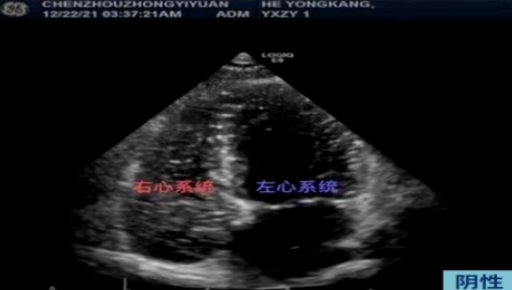

右心声学造影是经外周静脉注入造影剂,根据造影剂气泡的显影情况来协助诊断的检查方法。造影剂按正常途径不能通过肺毛细血管网,不能进入左心系统。因此可以根据显影顺序、途径和时间对某些结构和血流异常做出诊断和鉴别诊断。如果左右心系统存在异常通道(如房间隔缺损、卵圆孔未闭、肺动静脉瘘等),那么注入造影剂后左心腔会出现不同程度的微泡显影,因此能找到异常通道所在。

3、将配置好的微泡造影剂快速推注,待右房右室显影后嘱咐病人用力咳嗽或做 valsalva 动作,观察右心完全显影后左心内微泡显影的程度及时间。静止的单帧图像上左心内出现的微泡数量将右向左分流分为4个等级:

0 级:左心内没有微泡出现

1 级:左心内有 1-10 个微泡 / 帧,为少量右向左分流

2 级:左心内有 10-30 个微泡 / 帧,为中量右向左分流

3 级:左心内可见大于 30 个微泡 / 帧,或左心内几乎充满微泡,为大量右向左分流